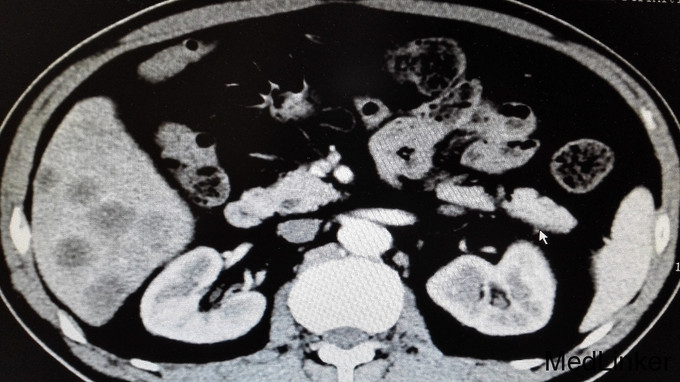

体格检查无特殊,未见明显阳性体征。 进一步完善辅助检查: 尿常规、大便常规、胸片、肝肾功能、血糖、血沉、风湿三项大致正常。血常规:白细胞11.7 ×10 9/L。右小腿MRI:1、右踝周围软组织信号改变,考虑炎症,请结合临床,必要时增强检查。2、右踝关节腔少许积液。血常规、心肌酶、电解质正常,心电图、心脏彩超未见明显异常。腹部CT平扫:1、肝实质多发稍低密度影性质待定,考虑转移瘤,建议进一步检查。2、肝左叶、尾叶多发低密度影性质待定,考虑囊肿。3、胆囊摘除术后。4、主动脉及右冠状动脉局部管壁钙化。AFP、CA199正常,CEA:6256.85ng/ml。输血前四项全阴性。全腹部增强CT提示:1、胃窦壁增厚,肝实质多发稍低密度影,考虑胃CA并肝内转移瘤可能,建议胃镜检查。2、肝左叶、尾叶多发囊肿。3、胆囊摘除术后。4、左肾囊肿。5、右肺下叶感染;左肺下叶纤维化病灶。6、主动脉及右冠状动脉局部管壁钙化。行胃肠镜检查提示慢性浅表性胃炎和盲肠占位,占位大小约40mm,已取病检。病检结果提示:盲肠中分化腺癌。

诊断:1、盲肠中分化腺癌并肝脏多发转移;2、右小腿软组织感染。 告知患者病情,目前无手术治疗指征,转肿瘤科行以化疗为主的肿瘤综合治疗。 患者经过再三考虑后,转省肿瘤医院消化肿瘤内科继续治疗。